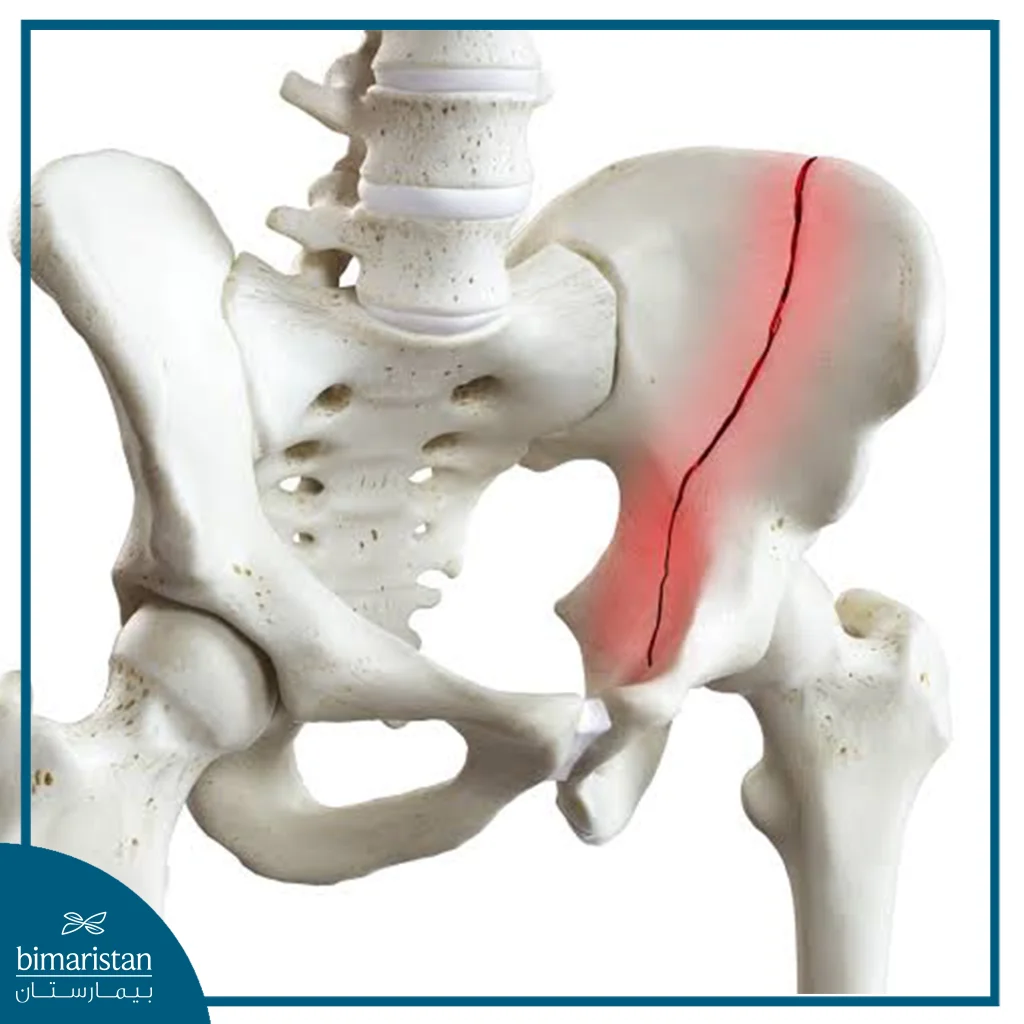

كسر الحوض هو انقطاع في أحد العظام التي تشكّل الحلقة الحوضية، والتي تربط العمود الفقري بالساقين وتُعدّ محوراً أساسياً لدعم الجسم أثناء الحركة والجلوس والوقوف، حيث يحدث الكسر عندما تتعرض هذه العظام لقوة تفوق قدرتها على التحمل، سواء نتيجة إصابة مباشرة كحوادث السير والسقوط من ارتفاع، أو بسبب هشاشة العظام التي تُضعف البنية العظمية وتجعلها أكثر عرضة للكسر حتى بعد سقوط بسيط، وقد يتراوح كسر الحوض بين شرخ بسيط مستقر لا يغيّر من موقع العظام، إلى كسر غير مستقر تتزحزح فيه العظام مسبباً أذية في الأوعية الدموية أو الأعضاء الداخلية.

تشمل الكسور الجزئية شقوقاً أو كسوراً لا تمتد عبر كامل العظم، وغالباً ما تكون أكثر استقراراً مقارنة بالكسور الكاملة أو المتزحزحة، يمكن علاج معظم هذه الكسور تحفظياً باستخدام دعامة أو تثبيت مؤقت، مع مراقبة دقيقة لتجنب تفاقم أي مضاعفات.